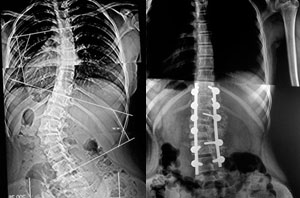

Me diagnosticaron escoliosis cuando tenía 13 años, en el año 2010 y ese mismo año me operaron en el mes de octubre. Al inicio, no me gustó la idea de la operación porque interfería con algunos planes que ya tenía en mente, pero sabía que si quería estar bien, tenía que sacrificarlos porque más importante era mi salud.  No muchos doctores saben de esta enfermedad, gracias a Dios conocí al Dr. Cárdenas que fue muy amable y amigable conmigo y me explicó con todo detalle como sería la intervención; así que más que miedo, sentía emoción porque llegara el día.

Después de mi operación, solo estuve internada 4 días. Tengo 11 tornillos en mi columna y ya llevo 5 años de operada; vivo una vida normal y soy feliz.

Caso de Escoliosis

Mi mama y Yo comenzamos a notar que mi columna estaba torcida, consultamos varias clínicas y sinceramente el único que nos explico con detalle mi enfermedad fue el Dr. Carlos Cardenas, pareciera que otro médicos no conocían esta enfermedad. Mi diagnostico fue escoliosis idiopática del adolescente. El único tratamiento para mi caso es con cirugía, tenia mucho miedo y me costo mucho decidir operarme.

Actualmente tengo 8 anos operada, y hago mi vida normal, hasta hago deporte, no tengo restricciones para nada. Quería agradecer infinitamente al Dr. Carlos Cardenas, por el excelente resultado pero sobretodo por su profesionalismo.